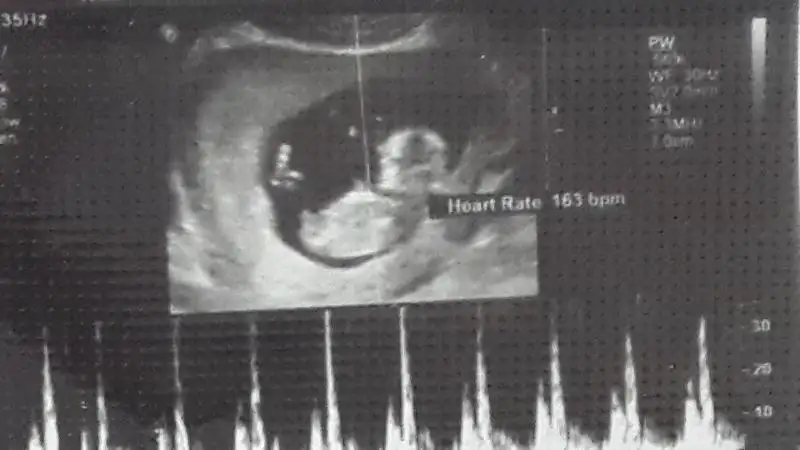

Bu da benim fistikkkkk....yuklendimi bilmiyorum..bence kiz.....sizce??? Dr tahmin soylemedi subat sonu gidicem artik o zaman oyrenirim kesin.ama bence kiz

Canm bu fotolarda gorunmuyo ama sen icini rahat tut o pipili dr gormustrde konusmustr merak etme orkidede bebde erkege brnzettik zaten sadece bi kisi rahimine gore kiz filan dedi hic yanilmadim diyo ama sende yanildi dr pipisini gormese yuzde doksan dermi hic git sen oglusuna en mavusinden bi cici al benim yerimede